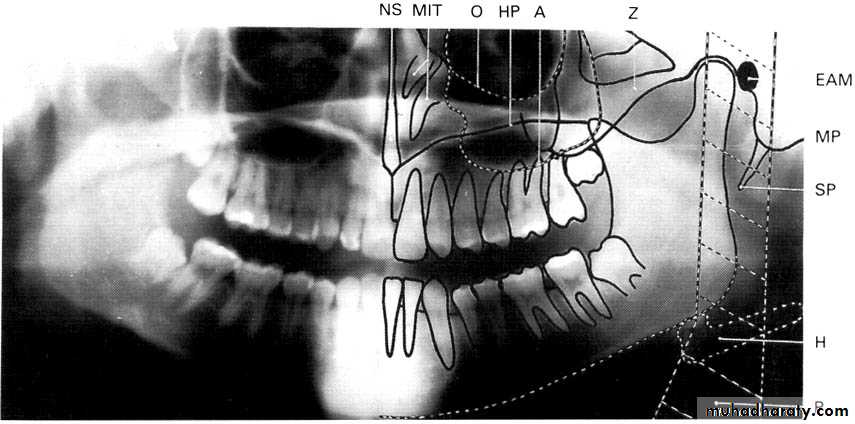

A dental panoramic tomograph showing the main real hard tissue shadows, including the plastic head support, drawn in on one side of the radiograph, NS — nasal septum,

MIT — middle and inferior turbinates, O — orbital margin, HP — hard palate, A — floor of antrum, Z — zygomatic arch, EAM — external auditory meatus, MP — mastoid process,

SP — styloid process, H — hyoid, P — plastic head support.